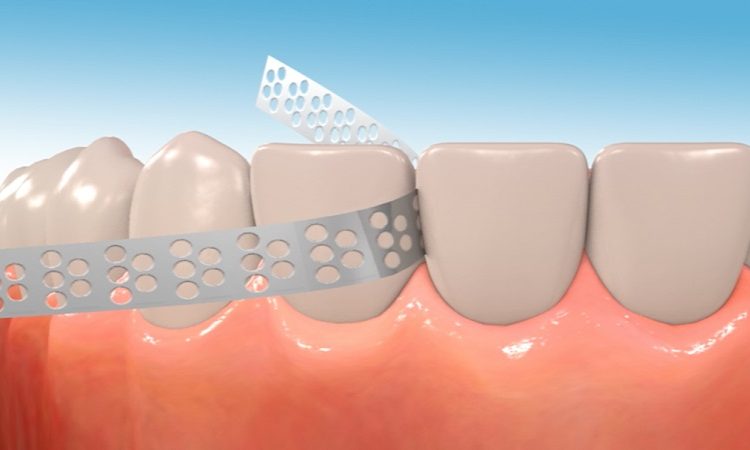

سمباده دندان چیست؟ سمباده دندان ابزاری است که هم متخصصین ترمیم و هم متخصصین ارتودنسی از آن برای اهداف مختلف بهره میگیرند. در ارتودنسی برای اینکه بتوان عرض دندانهای جلویی را کاهش داد، با استفاده از چنین ابزاری مینای آن را میسایند. نوار استریپها گروهی از همین سمبادهها هستند که کاربردهای متنوعی دارند. برای مثال